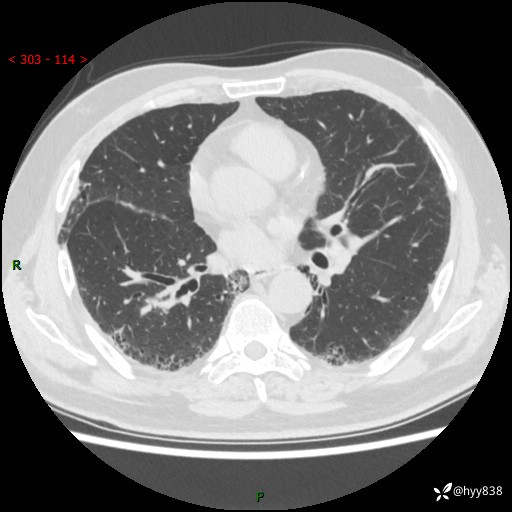

71岁/男,咳嗽伴气促半月。一年前肺手术史,又见两个结节,穿刺结果意外---结果公布~

【现病史】:患者半月前无明显诱因出现咳嗽、咳痰,为白色粘痰,无明显加重与缓解因素,伴气促,无发热,无大量脓痰,无胸痛、咯血,无哮鸣音,到我院就诊,胸部CT示右肺结节增大,并口服药物治疗无明显好转,具体用药不详,为求进一步治疗随来我院,经门诊以“孤立性肺结节”收入我科。 病程中患者精神、饮食可,睡眠不佳,大小便正常,体力下降,体重未见明显下降。

[既往史]:2022-06于当地第一人民医院确诊慢阻肺,现规律使用杰润(1次/日);2023-04-06于当地市第一人民医院行胸腔镜右肺上叶楔形切除术+右肺上叶切除术+淋巴结清扫术+胸膜黏连松解术,确诊为右肺鳞癌 pT2aN0M0 Ib期

【检查】:胸部CT平扫+增强